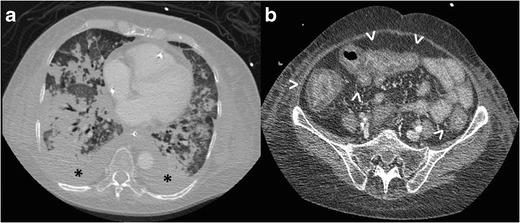

Radiologists seldom encounter parasitic diseases in their daily practice in most of Europe, although the incidence of these diseases is increasing due to migration and tourism from/to endemic areas. Moreover, some parasitic diseases are still endemic in certain European regions, and immunocompromised individuals also pose a higher risk of developing these conditions. This article reviews and summarises the imaging findings of some of the most important and frequent human parasitic diseases, including information about the parasite's life cycle, pathophysiology, clinical findings, diagnosis, and treatment. We include malaria, amoebiasis, toxoplasmosis, trypanosomiasis, leishmaniasis, echinococcosis, cysticercosis, clonorchiasis, schistosomiasis, fascioliasis, ascariasis, anisakiasis, dracunculiasis, and strongyloidiasis. The aim of this review is to help radiologists when dealing with these diseases or in cases where they are suspected. Teaching Points • Incidence of parasitic diseases is increasing due to migratory movements and travelling. • Some parasitic diseases are still endemic in certain regions in Europe. • Parasitic diseases can have complex life cycles often involving different hosts. • Prompt diagnosis and treatment is essential for patient management in parasitic diseases. • Radiologists should be able to recognise and suspect the most relevant parasitic diseases.

在欧洲大部分地区,放射科医生在日常工作中很少遇到寄生虫病,尽管由于往返于流行地区的移民和旅游活动,这些疾病的发病率正在上升。此外,某些寄生虫病在欧洲的某些地区仍然流行,免疫功能低下的个体感染这些疾病的风险也更高。本文回顾并总结了一些最重要且常见的人类寄生虫病的影像学表现,包括有关寄生虫生命周期、病理生理学、临床表现、诊断和治疗的信息。我们涵盖了疟疾、阿米巴病、弓形虫病、锥虫病、利什曼病、棘球蚴病、囊尾蚴病、华支睾吸虫病、血吸虫病、片形吸虫病、蛔虫病、异尖线虫病、麦地那龙线虫病和粪类圆线虫病。这篇综述的目的是在放射科医生处理这些疾病或怀疑患有这些疾病的病例时提供帮助。教学要点 • 由于人口迁移和旅行,寄生虫病的发病率正在上升。 • 某些寄生虫病在欧洲的某些地区仍然流行。 • 寄生虫病可能具有复杂的生命周期,通常涉及不同的宿主。 • 及时诊断和治疗对于寄生虫病患者的管理至关重要。 • 放射科医生应该能够识别和怀疑最相关的寄生虫病。